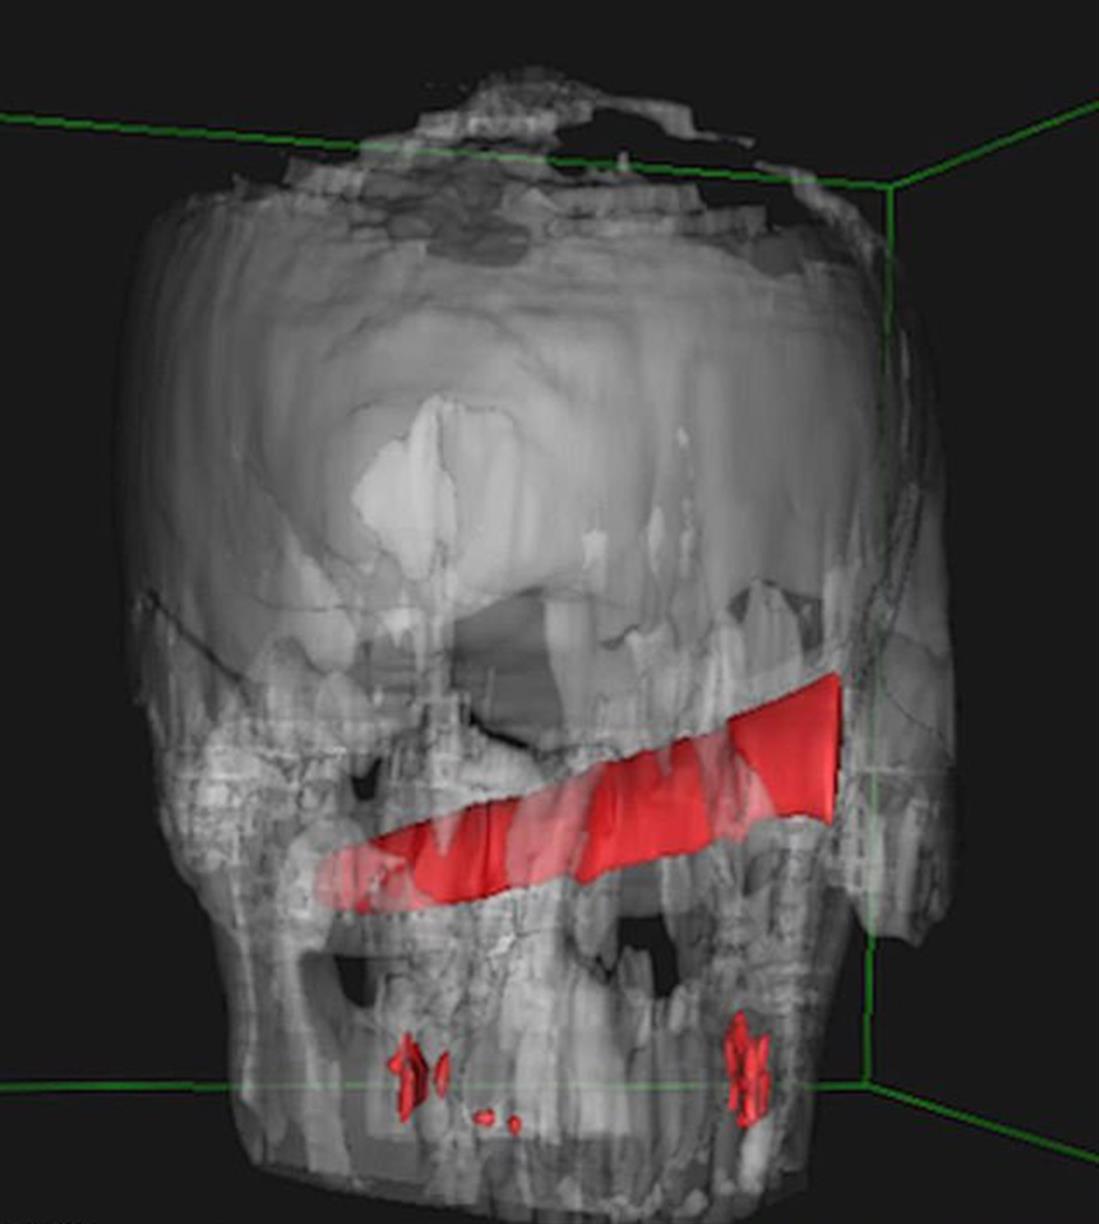

Συγκλονίζει η ακτινογραφία του κεφαλιού ενός άνδρα πάνω στο οποίο ήταν καρφωμένο ένα μαχαίρι μήκους 10 εκατοστών, τέσσερις μέρες αφού δέχθηκε μαχαιριά!

Σύμφωνα με τους θεράποντες ιατρούς, η λεπίδα μπήκε κάτω από το μάτι του και έμεινε εκεί λόγω του ότι «σκάλωσε» στο κόκκαλό του.

Οι γιατροί δημοσίευσαν τις ακτινογραφίες, εξαιτίας του πρωτοφανούς γεγονότος.